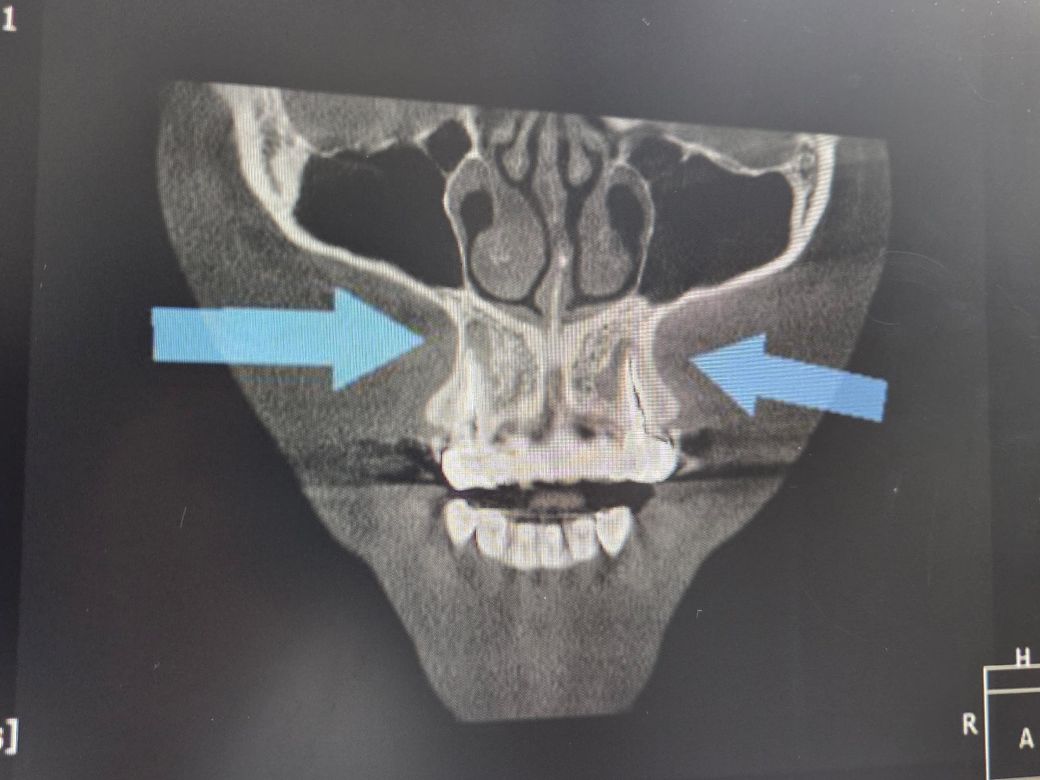

스켈링 하러 갔다가 이리저리 사진 찍으시더니 양송곳니 뿌리에 고름이 많이 찼다고 뿌리를 자르고 신경치료를 다시 해야된다고 하시네요. 신경치료를해서 아프진 않습니다.

사진으로 봤을 경우 치근단에 병소가 보입니다 신경관의 감염으로 인해서 생긴 염증이라면 재신경치료가 필요할수 있습니다.

1. 엑스레이상으로 염증이 보이기 때문에 처치는 필요할 것 같습니다.

2. 보철 비용 때문에 부담되신다면 재신경치료말고 치근단 절제술을 해볼 수 있으나 해부학적 구조에 따라서 힘든 케이스 일 수도 있습니다.

일단은 증상이 없다면 정기적으로 관리를 하시면서 지켜보시던지 치료를 하게되면 치근단 절제술을 해보셔야될것같습니다.